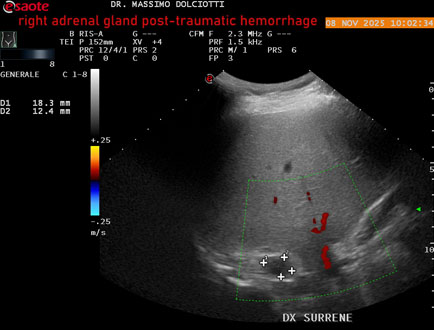

Data inserimento: 10/11/2025

Ecografia del: 08/11/2025

Strumento: Esaote MyLab Eight

Sonda: Convex Multifrequenza 1-8 MHz

Età Paziente: M 49 anni

Motivazione dell'esame: follow up per emorragia al surrene destro post-traumatica (incidente stradale).

Commento all'esame: le immagini ed il video documentano in sede surrenalica destra, formazione ipo-anecogena, a margini definiti, ovalare, delle dimensioni di 38,6 x 19,7 mm, da ricondurre ad emorragia post-traumatica.

Conclusioni: emorragia post-traumatica al surrene destro (post-traumatic hemorrhage to the right adrenal gland).

Presentazione: Dr. Massimo Dolciotti - Ancona

Elaborazione digitale: Andrea Dini - Ancona